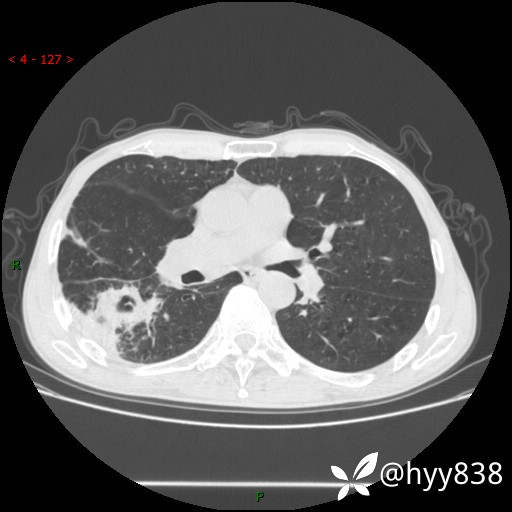

老年男性,肺团片状占位+体重下降,肿瘤 VS 真菌 VS 细菌,看看你的意见--结果公布~

简要病史:患者7天前无明显诱因出现咳嗽咳痰,咳绿色、褐色痰,吸烟后加重,伴心慌、胸闷,无畏寒发热,无头晕头痛,无鼻塞流涕,无痰中带血及咯血,无胸痛、呼吸困难,无全身酸痛,为求进一步诊治于我院就诊,门诊完善胸部CT提示“右下肺团片状影,考虑肿瘤?感染?”,门诊以“咳嗽待查”收住入院。 起病以来,患者精神、饮食、睡眠尚可,大、小便正常,体力下降,体重下降8斤。空腹血糖:6.42mmol/L。

辅助检查:CT

临床诊断:肿瘤?感染?

讨论:病变性质?

增强动脉期